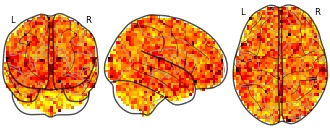

Movie clips: Reproducibility map OD p0.010 3 Happiness

niftiUpdated Jan 9, 2018+ more versions Share

EmailClick to copy linkLink copied Cite(2018). Movie clips: Reproducibility map OD p0.010 3 Happiness [Dataset]. http://identifiers.org/neurovault.image:58806niftiAvailable download formatsUnique identifierhttps://identifiers.org/neurovault.image:58806Dataset updatedJan 9, 2018License

Cite(2018). Movie clips: Reproducibility map OD p0.010 3 Happiness [Dataset]. http://identifiers.org/neurovault.image:58806niftiAvailable download formatsUnique identifierhttps://identifiers.org/neurovault.image:58806Dataset updatedJan 9, 2018LicenseCC0 1.0 Universal Public Domain Dedicationhttps://creativecommons.org/publicdomain/zero/1.0/

License information was derived automaticallyDescription - a